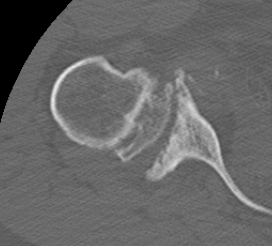

Levigne and Franceschi Classification

Three main patterns

| Type 1 | Type 2 | Type 3 |

|---|---|---|

|

Upward migration Superior glenoid wear |

Concentric medial migration Deficient medial bone stock |

Destructive |

Due to rotator cuff insufficiency Most common pattern |

||

Destructive RA